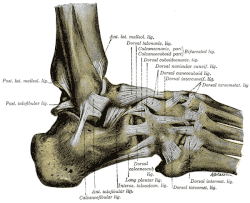

Das Sprunggelenk mit seinen Bändern

Das obere Sprunggelenk des Menschen (es gibt auch ein unteres Sprunggelenk [USG] unterhalb des Sprungbeins) besteht aus dem Wadenbein (Fibula), dem Schienbein (Tibia) und dem Sprungbein (Talus). Straffe Bänder halten die mit Knorpeln überzogenen Gelenkenden dieser Knochen zu einem Gelenk zusammen: Das vordere und das kräftigere hintere Syndesmosenband verbinden Waden- und Schienbein zur Sprunggelenkgabel; der Schaft des Wadenbeins und des Schienbeins am Unterschenkel darüber sind durch das funktionell gleichwertige flächige Zwischenknochenband (Membrana interossea) verbunden. Das in die Sprunggelenkgabel eingepasste Sprungbein wird durch die Außen- oder Seitenbänder (Ligamentum fibulotalare anterius, Ligamentum fibulocalcaneare und Ligamentum fibulotalare posterius) und das etwa dreieckige Innenband (Ligamentum deltoideum) beweglich, aber stabil gehalten. Die aktive Stabilisierung des oberen Sprunggelenkes erfolgt über die peronealen (fibularen) und tibialen Sehnen parallel zum Bandapparat und über die gelenkübergreifenden Streck- und Beugesehnen mit der Achillessehne. Die Lastübertragung des Fußes auf den Unterschenkel erfolgt ausschließlich über das Sprungbein und die untere Gelenkfläche des Schienbeins. Die Knöchel dienen dabei der seitlichen Führung des Gelenks. Der Innenknöchel ist integraler Bestandteil des breiten, unteren Schienbeinendes, während der Außenknöchel die gelenkseitig überknorpelte Spitze des Wadenbeins darstellt.